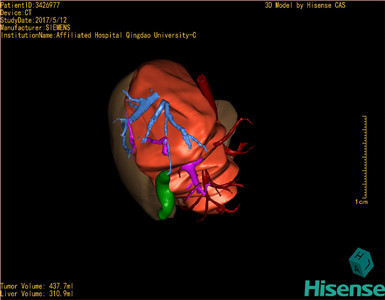

CT结果输入海信CAS系统后行3D重建及手术规划后,肿瘤位于右肾上腺区并周围淋巴结肿大,与血管关系紧密,建议化疗,静脉高营养、全量补液及对症支持治疗,患儿恢复良好,伤口无渗血渗液,无红肿疼痛,于2017-5-16出院。

术前三维重建:

重建图片